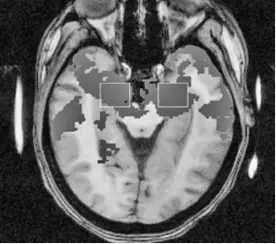

Как побудить людей сразу довериться нам? Какие особенности мозга заставляют нас верить в то, что не соответствует истине? Как побеждать в спорах, используя тактику новорожденных младенцев?